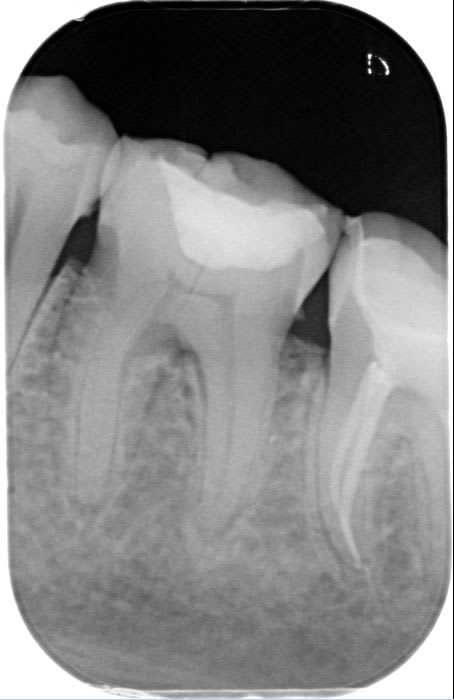

J'ai dévitalisé une 36 nécrosée à cause d'une fêlure en linguale... La patiente n'avait pas eu de signes d'appel avant les fortes douleurs dues à la nécrose.

Lors de la dévitalisation, j'ai été surprise à la radio par la largeur du trait de fêlure qui ne correspond pas à ce que je vois avec mes loupes ( zeiss x2.5)

Je n'ai pas non plus de fêlure au niveau du plancher pulpaire mais je vois bien une fêlure qui continue un peu sous la gencive linguale.

surtout que ma 36 n'a pas de longues racines et présente 4 canaux fins pour les futurs inlay cores...

A priori elle est pas fêlée mais fendue si j'en crois la radio lime en place....

Donc pas possible de garder la dent en l'état.

Reste la séparation de racines comme indiquée plus haut...

Possibilité c'est de faire un inlay core en U qui solidariser les deux racines et laisse un accès aux brossettes.

Pas de précipitation d'autant que le trait de fracture rejoint la racine mésial (c'est peut être l'incidence de la rx qui fait croire ca) donc séparer les racines et mettre sous provisoire et attendre de 6 à 12 mois

Juste un truc: ce sera casse gueule et il y a risque de fracture d'une des racines surtout la mesiale qui est en général en arc et fine...